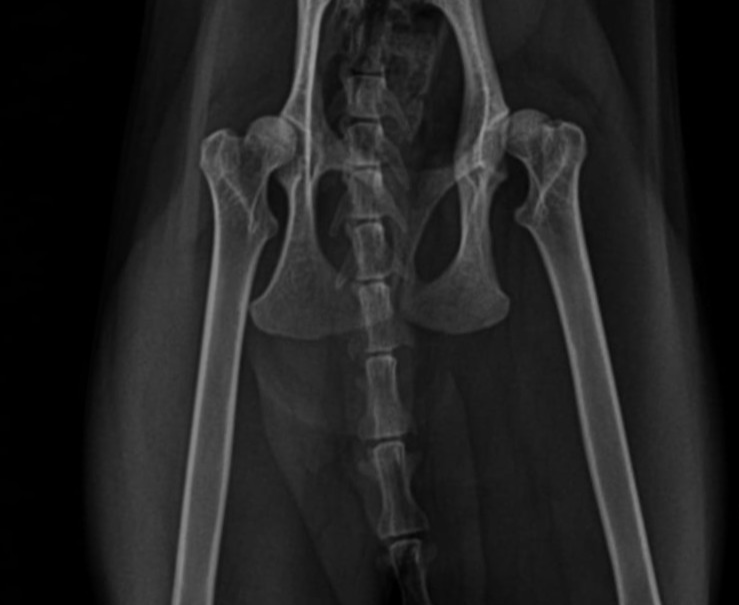

A 1.5-year-old male Scottish Shorthair cat was presented to the clinic with a history of progressive hindlimb lameness and difficulty jumping.

No history of trauma was noted. The condition gradually worsened, affecting both hindlimbs mor severe in the right hind limb

• Bilateral hindlimb lameness with a “bunny-hopping” gait pattern

• Pain and crepitus upon hip manipulation

• Positive Ortolani sign confirming hip joint laxity

Bilateral FHO was recommended starting with the right most affected limb and the other to be scheduled after 2 months